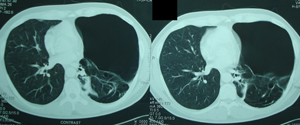

Εικόνα 2δ

Αξονική τομογραφία του θώρακος. Τομή πάνω από το επίπεδο του

διαφράγματος. Διακρίνεται περισσότερο πνευμονικό παρέγχυμα, ενώ

συνεχίζουν να διακρίνονται αερώδεις κύστες.

Εικόνα 2ε

Αξονική τομογραφία του θώρακος. Τομή στο επίπεδο του διαφράγματος.

Μεικτή εικόνα, αερωδών κύστεων και πνευμονικού παρεγχύματος.